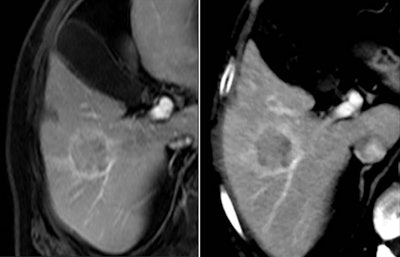

This case of a liver tumor was examined with a Somatom Perspective scanner from Siemens Healthcare. The volume-rendered technique (VRT) image highlights multiple liver lesions and fine details of the mesenteric arteries. Image courtesy of Diagnosezentrum Favoriten, Vienna.